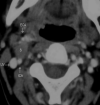

Results: The schwannomas were solitary, well-circumscribed, and medial to the carotid sheath. Seven were hypoattenuated to skeletal muscle on CT with poor postcontrast enhancement, 4 were isoattenuated, and a single lesion showed intense heterogeneous enhancement. At MR imaging, they were heterogeneously bright on T2WI with intense inhomogeneous postgadolinium enhancement. The ICA was displaced anteriorly in 9 patients with a component of lateral displacement in 8 of these patients. The ICA was in a neutral position in 2 patients and posterolaterally displaced in 1 patient. A single patient demonstrated separation of the ICA and IJV. There was splaying of the carotid bifurcation in 4 patients.